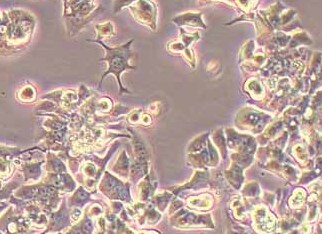

人食管癌细胞系OE19(STR鉴定正确) OE19 human esophageal cancer cells

形态:上皮细胞样

生长特征:贴壁生长